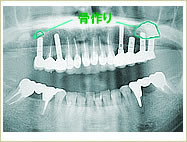

●骨作りを行った症例

38歳 女性 インプラント埋入数:6本 画像拡大

治療前

治療前   治療前

骨作り

骨作り 骨作り